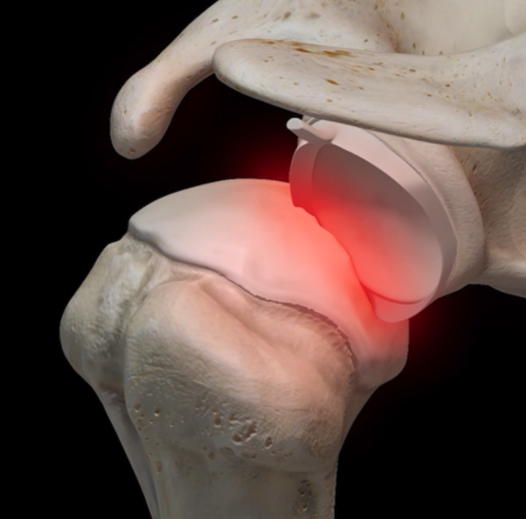

L’épaule est l’articulation la plus mobile du corps. Elle ressemble à une boule qui glisse sur une assiette plate. Elle est dite peu congruente, cela veut dire que la boule n’est pas spontanément stable sur l’assiette. La boule représente la tête de l’humérus, et l’assiette la glène (partie de l’omoplate qui s’articule avec l’humérus). La tête est stabilisée en face de la glène par le bourrelet glénoïdien qui s’insère tout autour de la glène.

On parle de luxation lorsque la tête de l’humérus n’est plus en face de la glène. Dans plus de 90% des cas, les luxations sont antérieures, la tête humérale passe alors en avant de la glène.

- l’encoche de Malgaigne ou Hill Sachs : en se luxant, la tête humérale vient en conflit avec la partie antérieure de la glène. Celle-ci peut alors laisser une empreinte sur la partie postéro-supérieure de la tête,

- la déchirure du bourrelet glénoïdien,